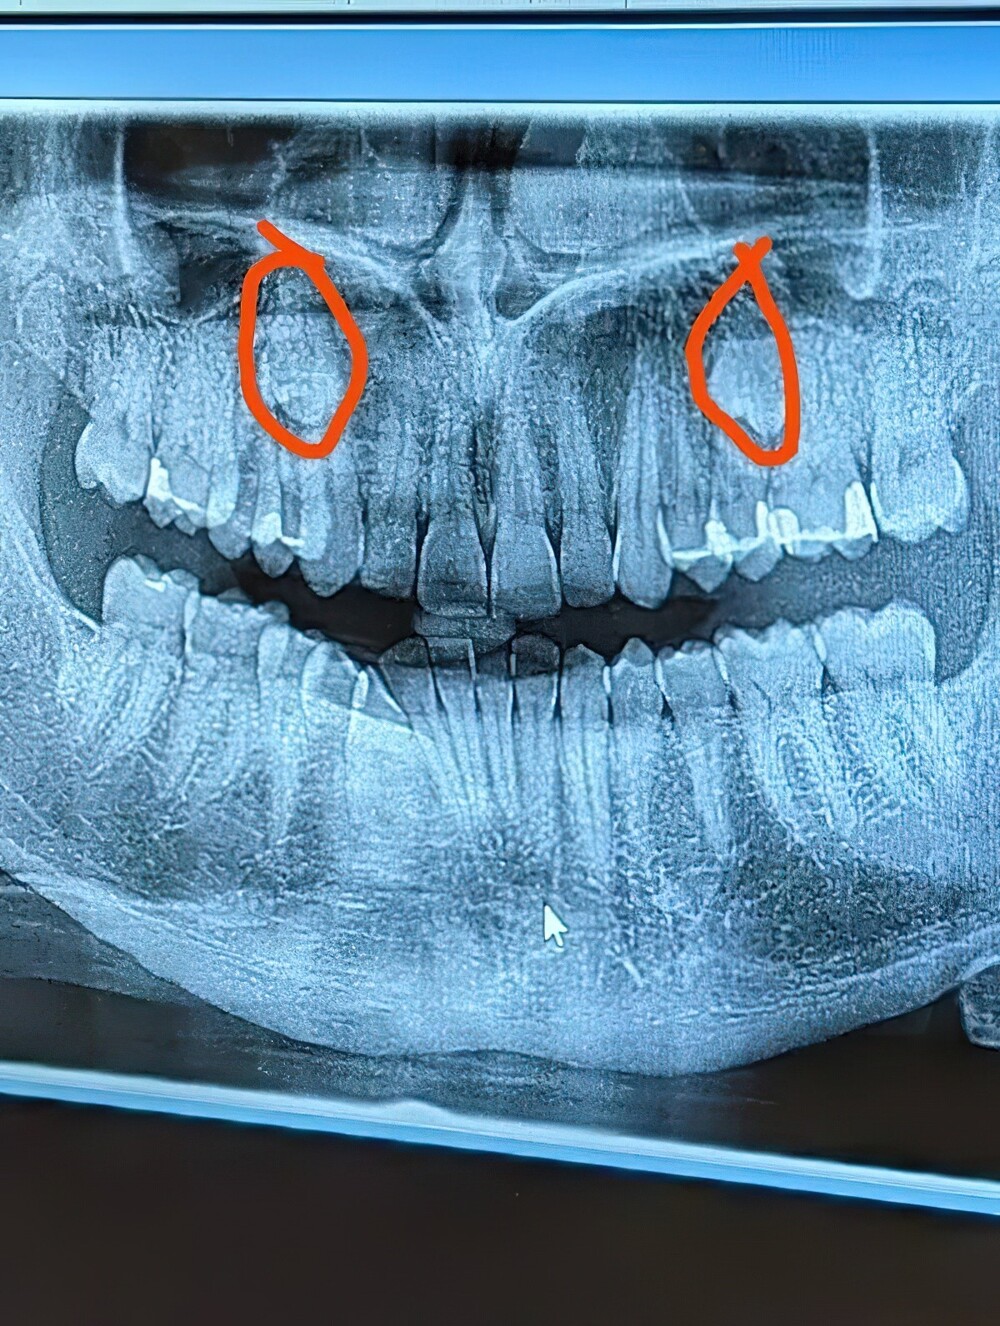

17. And finally, this man, whose hands differ from one another in size, shape and even color

Today I went to the doctor for the first time about this. Fingers at I've always been knotty and a little crooked, but over the last couple of years the joints on the right hand began to swell and ache under certain loads. It's getting worse, so I decided to look into the problem. My therapist was very worried and immediately sent me for an x-ray. I write here just to cheer yourself up a bit.